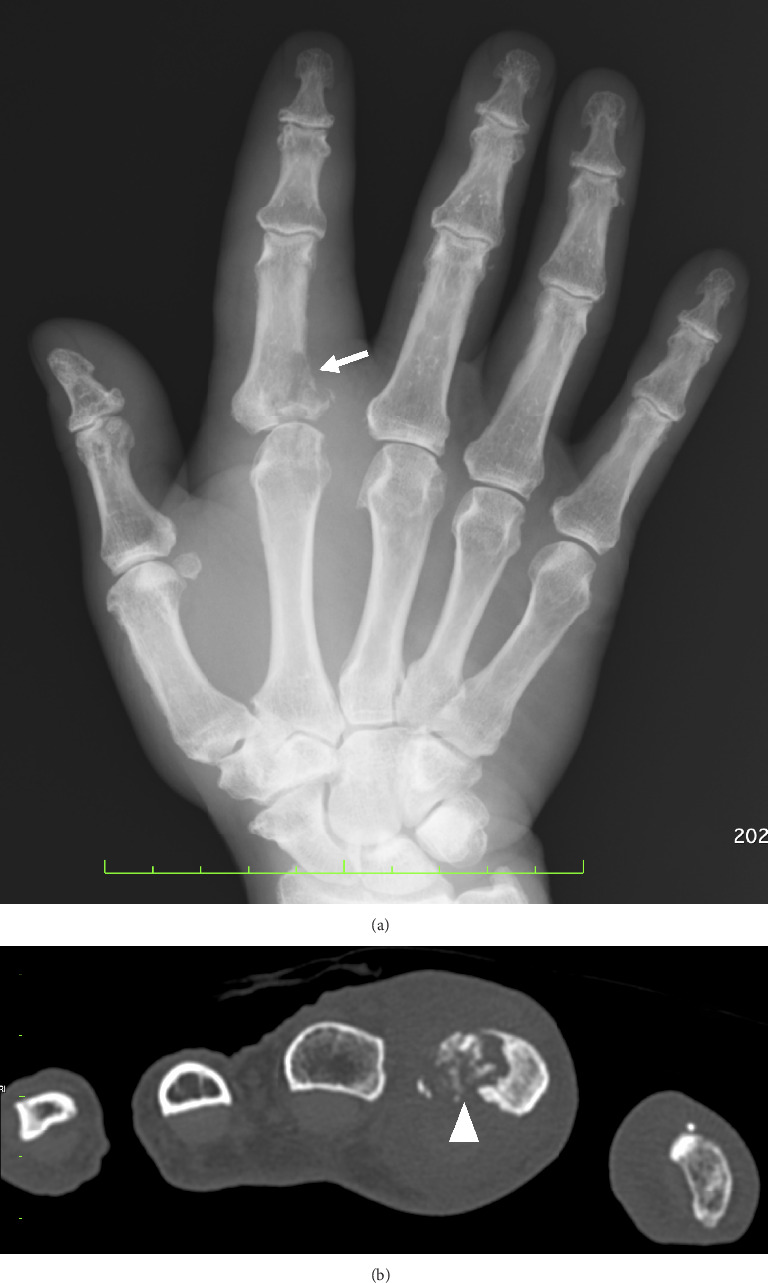

Background: Nontuberculous Mycobacterium (NTM) infections affecting musculoskeletal structures are rare, particularly in patients with well-controlled rheumatoid arthritis (RA). This case is reported to highlight the potential risk of focal tenosynovitis due to Mycobacterium intracellulare following intra-articular glucocorticoid injection. Case presentation: A 79-year-old man with well-controlled RA developed tenosynovitis with bone destruction in the right index finger metacarpophalangeal joint following a single intra-articular injection of triamcinolone acetonide. Despite antibiotic treatment, the condition progressively worsened. Synovectomy revealed Mycobacterium intracellulare infection involving both flexor tendons, joint space, and bone marrow. The patient regularly engaged in gardening activities without protective gloves. Conclusion: This case highlights the importance of considering NTM infection in the differential diagnosis of persistent monoarthritis that worsens after intra-articular glucocorticoid injection, especially in patients with exposure risk factors such as gardening.